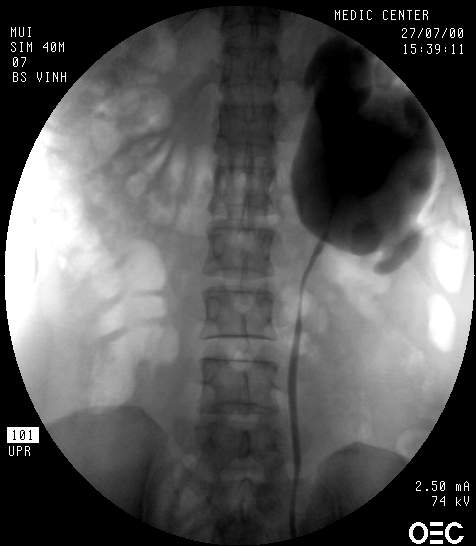

+ Nội soi bàng quang và chụp bể thận ngược dòng

• Xác định chiều dài của niệu quản bị ảnh hưởng

• Đặt stent JJ để giải áp tạm thời sự tắc nghẽn

Vài hình ảnh hẹp Khúc nối bể thận - niệu quản